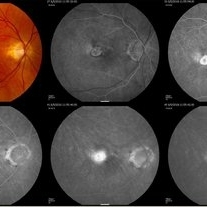

Active Polypoidal Choroidal Neovascularization

Feb 9 2022 by Jeffrey Barker

80-year-old male with active polypoidal neovascularization.

Photographer: Jeffrey P. Barker, Retina Vitreous Surgeons of CNY.

Condition/keywords: Active Polypoidal Choroidal Neovascularization, choroidal neovascularization (CNV)